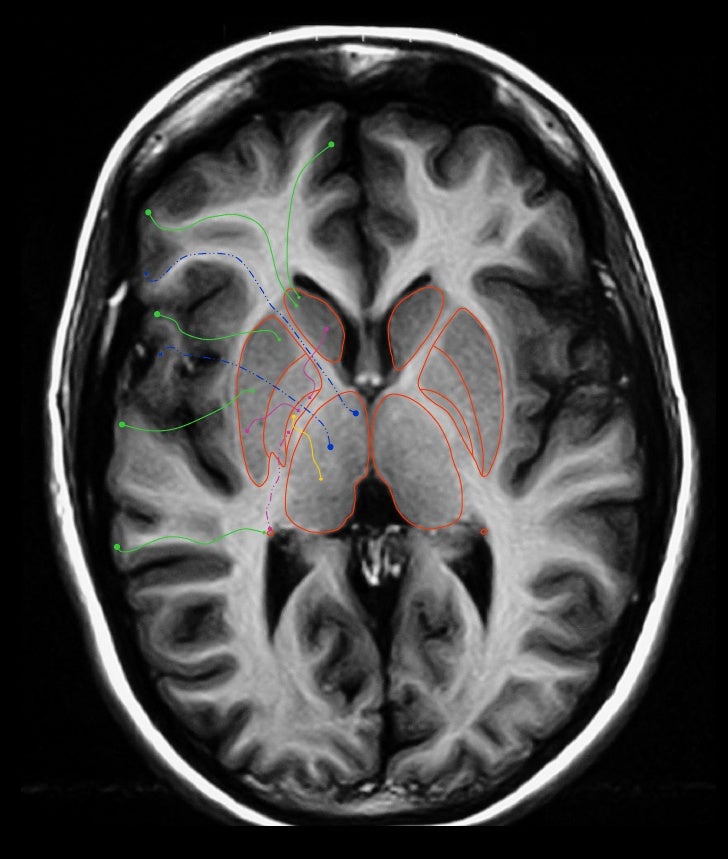

Anatómicamente los ganglios basales son masas de sustancia gris en el telencéfalo que incluyen: 1) núcleo (n) caudado, 2) n lenticular (formado por el n putamen y el globo pálido externo e interno, 3) y la amígdala. Funcionalmente se relacionan a través de múltiples conexiones con núcleos próximos que incluyen al núcleo subtalámico.

Los ganglios basales son un grupo de núcleos interconectados que participan en funciones motoras y no motoras. En términos anatómicos, el término se refiere a los siguientes núcleos: caudado, putamen, globo pálido, nucleus accumbens septi y tubérculo olfatorio, todos ellos localizados de manera topográfica en la "base" del cerebro (fig. 14-2).

Page ID. Los ganglios basales son un grupo de núcleos subcorticales, es decir, grupos de neuronas que se encuentran debajo de la corteza cerebral. Los ganglios basales están compuestos por el estriado, que consiste en el núcleo caudado y el putamen, el globus pallidus, el núcleo subtalámico y la sustancia nigra.